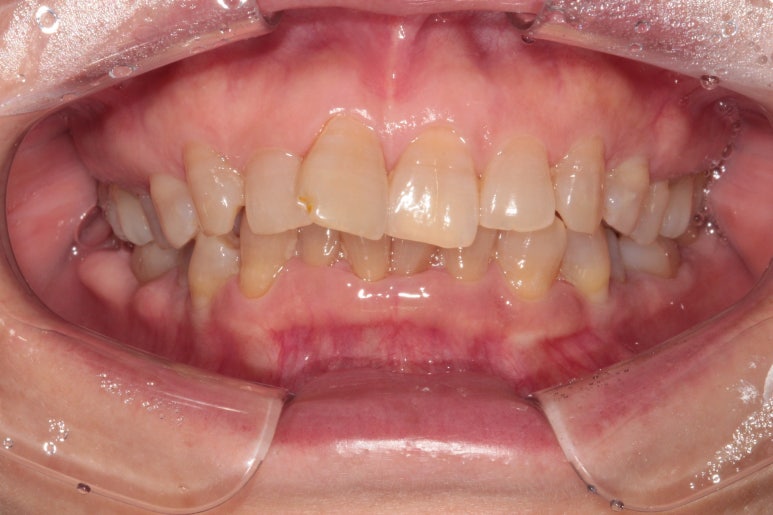

앞니가 좀 삐뚤어져 있었습니다.

보통 아래 앞니보다는 위 앞니가 삐뚤빼뚤 할 때 상담차 오시곤 하는데요,

아무래도 환자의 대부분이 성인이다보니 그런 것 같아요.